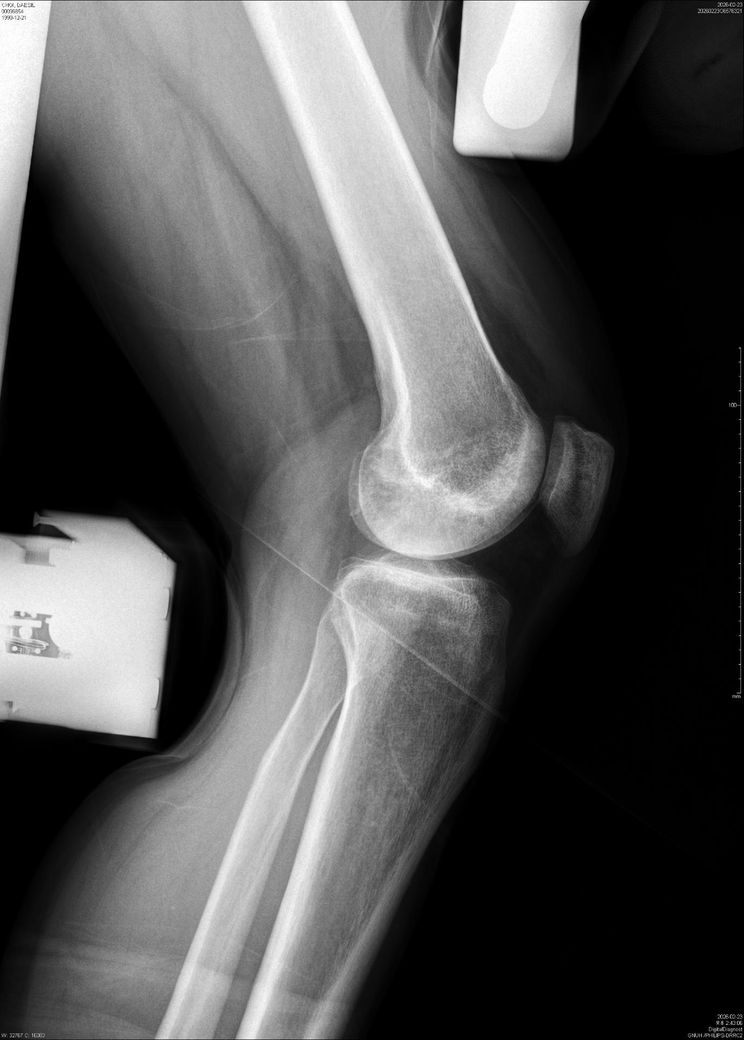

무릎 동요도를 알수있을까요?(X-RAY)사진 첨부

반월판연골과 십자인대 수술한 부위가 6개월이 지난 현재도 무릎이 아파서

어제 촬영하였는데, 정확한 소견은 못듣고 씨디만 받아서요..

혹시 무릎 동요도를 알수있을까요?

• 1번 째 사진

이 X-ray는 뼈 정렬·고정물 위치만 볼 수 있어, “무릎 동요도(십자인대 안정성)”는 판단할 수 없습니다.

동요도는 Lachman, Pivot shift 같은 이학적 검사나 MRI로 확인해야 합니다.

수술 6개월 후에도 통증이 지속되면 인대 이완, 반월상연골 재손상, 연골 손상 가능성도 있습니다.

정형외과에서 직접 진찰 + 필요 시 MRI를 꼭 권유드립니다.